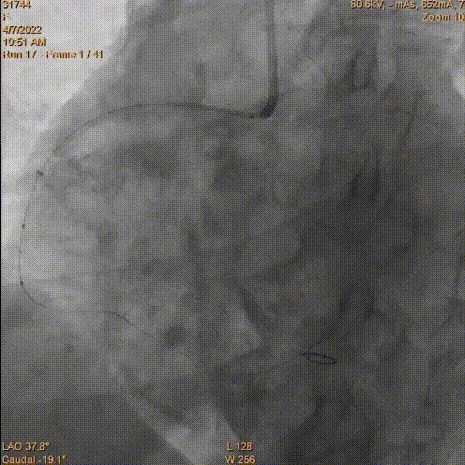

2.5×12mmSprinter球囊以12atm×5s、14atm×5s扩张RCA中远段狭窄病变

Telescope™的操作过程及优势

预扩球囊送入困难,通过迂曲血管段轻度受阻,为减少药物球囊释放时间,增加手术成功率,送入Telescope™导引延长导管,然后沿导引延长导管快速送入2.75×16mm药物球囊至病变处。

2.75×16mm Vesselin药物球囊

以12atm×40s充分扩张